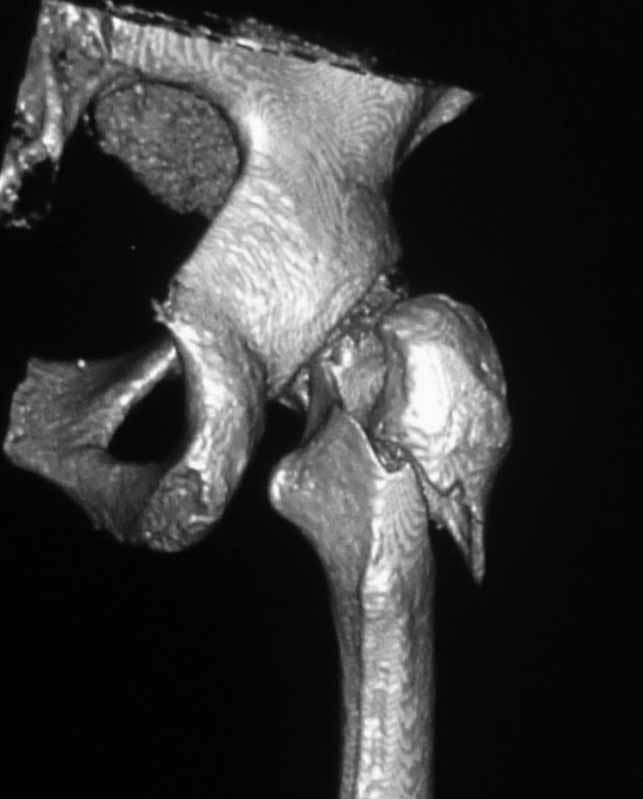

Пациентка 53 лет. ДТП 09.01.12: сочетанная травма: перелом 2-5 ребер справа, ушиб легких;

перелом обеих лонных костей без смещения; закрытый перелом проксимального конца правой

бедренной кости; открытый оскольчатый внутрисуставной перелом проксимальных концов

костей правой голени.

Бедро одномоментно делать не стал, не было уверенности в наличии перелома на уровне шейки. Во время операции смотрел тазобедренный сустав под ЭОПом,

головка неподвижна. После операции повторили КТ, стало очевидно, что имеется субкапитальный перелом. Что делать, остесинтез или протезирование? Если остеосинтез, то чем? Заранее благодарен за советы.